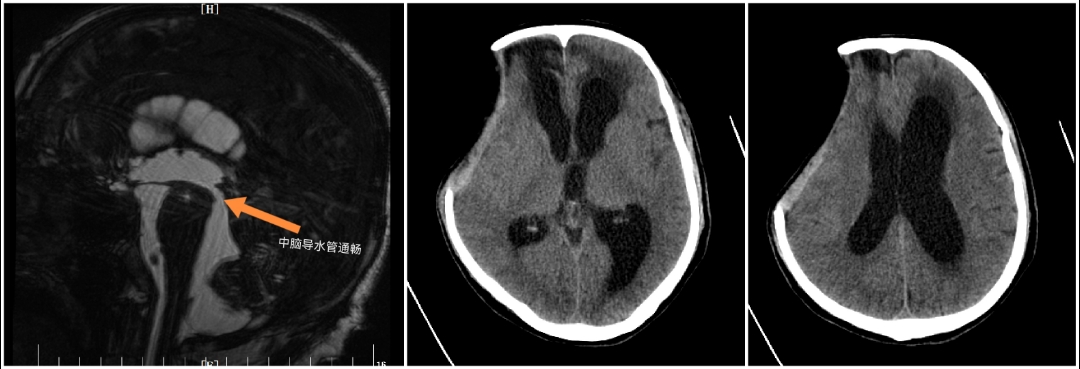

近期陕西省核工业二一五医院神外监护室完成西北首例低颅压性脑积水ProSA+ProGAV系统分流手术。患者老年男性,半年前因重型颅脑损伤在本院行开颅手术治疗,术后意识清楚,好转出院。本次因智力减退步态迟缓10天入院。入院头颅CT及核磁提示(脑室系统扩大,周围可见间质水肿;中脑导水管通畅)。

患者临床症状表现为痴呆、步态不稳、记忆力减退、大小便失禁症状。既往有颅内感染病史,腰穿测压力为70mmH2O,脑脊液蛋白含量高。在颅骨修补手术后,患者意识障碍较前加重。术后头颅CT(脑室系统较前扩大)。采取侧脑室额角穿刺安置Ommaya囊,通过侧脑室穿刺管内水柱高度判断侧脑室内压力,测患者脑室内压力为60mmH2O。诊断为低颅压性脑积水。